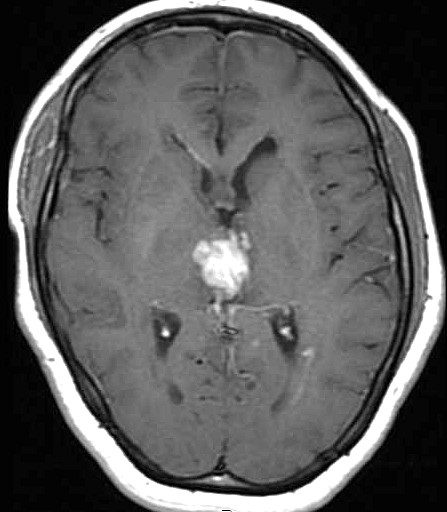

| Fem. 17a. |

| Nódulo sólido homogêneo preenchendo o III ventrículo, com limites precisos, com hipossinal em T1 e hipersinal em T2 e FLAIR, que se impregna por contraste paramagnético. Lesão menor implantada no assoalho do IV ventrículo provavelmente representa disseminação por via liquórica. |

| CORTES AXIAIS, T1 COM CONTRASTE | ||

| F. 17a. Tumor teratóide rabdóide atípico de III ventrículo. RM | HE | VIM, GFAP | HHF35, desmina, 1A4 | AE1AE3, EMA |